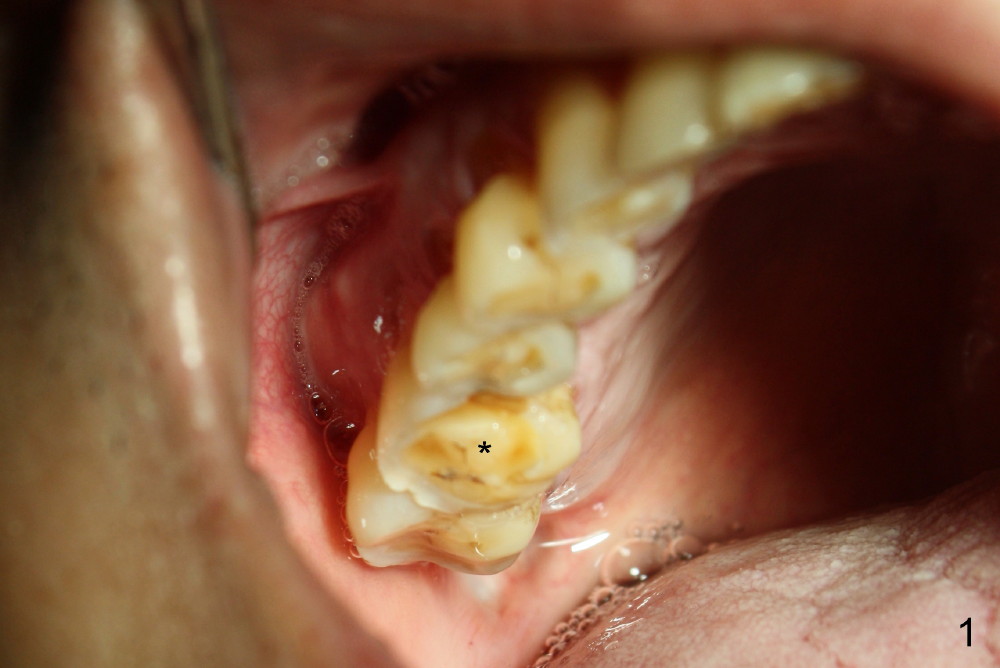

病人回来时说已经不太痛了,但是颊侧近中根尖仍有轻度肿胀,触痛(图三箭头),反复告诉他不处理不行,他强调采纳最保守治疗,不愿拔牙植牙,左下第二磨牙植牙(图四I)不好用,好像与真牙不一样。其实他牙齿磨耗尤其严重(图一至图四显示四个象限后牙,*代表第一磨牙),两个磨牙牙冠一定要有金属合面,否则陶瓷会断裂,而且牙冠容易脱落。左下第二磨牙植牙折腾部分原因是对合牙(左上第二磨牙)往下掉(supraerupted,图二S),没有空间放植牙,基牙和牙冠。